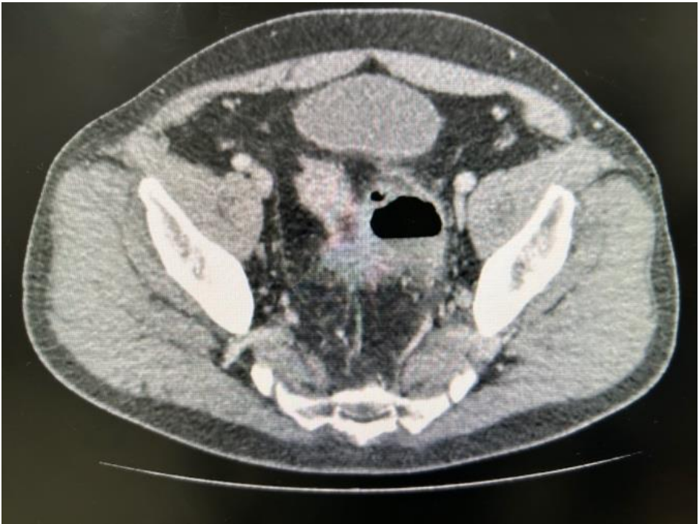

Realizada tomografia computadorizada de abdome com contraste, mostrando imagem de coleção de 5,6cm de tamanho justa-cólico, sem pneumoperitônio livre, conforme imagem abaixo: